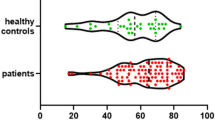

Summary data on outcomes are presented in Table 2. There was strong evidence of differences in GCS score at discharge, functional outcome by mRS score, and mortality between the AB and CD groups. In the CD group, compared with the AB group, the GCS score at discharge was higher, functional outcome by mean mRS score was higher, the mortality rate was lower, and good outcome by dichotomized mRS score was more likely (Fig. 4). Length of stay and presence of stroke on final in-hospital imaging were not different between groups. Nonsurvivors had significantly worse ‘ABCD’ categorization than survivors.

Functional Outcome

Functional outcome on an ordinal mRS was significantly better in the CD group compared with the AB group (p < 0.01). Univariate and multivariate analyses of clinical variables associated with functional outcomes, as determined by dichotomized mRS scores, are shown in Table 3. In univariate analyses for functional outcome, by using dichotomized mRS scores, unadjusted odds for poor outcome were 0.38 (95% confidence interval [CI] 0.15–0.96) for good WFNS grade vs. 2.18 (95% CI 1.06–4.45) for poor grade, 0.43 (95% CI 0.20–0.94) for good HH grade vs. 3.50 (95% CI 1.41–8.67) for poor grade, 1.15 (95% CI 0.55–2.42) for absence of fever vs. 1.07 (95% CI 0.52–2.22) for presence of fever, 0.50 (95% CI 0.23–1.07) for CD category vs. 2.86 (95% CI 1.21–6.76) for AB category.